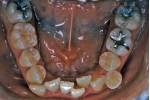

日本矯正歯科学会専門医課題症例(第4症例)

カテゴリー:ClassⅡ division 2 malocclusion (Overbite 5mm以上; 抜歯症例)

しかし、出題基準にも書いてあるように、このケースは欧米の白人によく見られるケースで、東洋人にはきわめて稀である。そこで類似ケースとして過蓋咬合(かがいこうごう)のケースを代替えとして認めるという配慮をしている。過蓋咬合とは非常に強く深く咬んでいる状態を言う。Overbiteとは前歯の垂直的な重なり具合を示す数値で、5mm以上だと上の前歯が下の前歯をほとんど覆い尽くしている感じになるので、前から見ると下の前歯はほとんど見えない状態になる。こういう状態が典型的な過蓋咬合である。典型的なclassⅡ,division 2のケースは過蓋咬合を合併している。

| 治療中